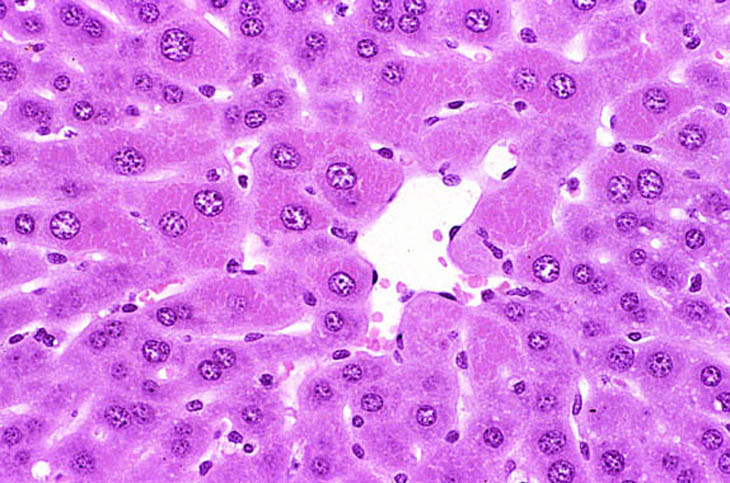

Centrilobular hepatocytes have alterations in their cytoplasm characterized by increased eosinophilia with a fine to coarse flocculent texture. In some situation the appearance may be more homogeneous. The terminology that might be used for this change includes hyaline change, hyaline degeneration, or cytoplasmic alteration. If the latter term is used, the change must be adequately described in a pathology narrative since the term cytoplasmic alteration has different connotations to different individuals.